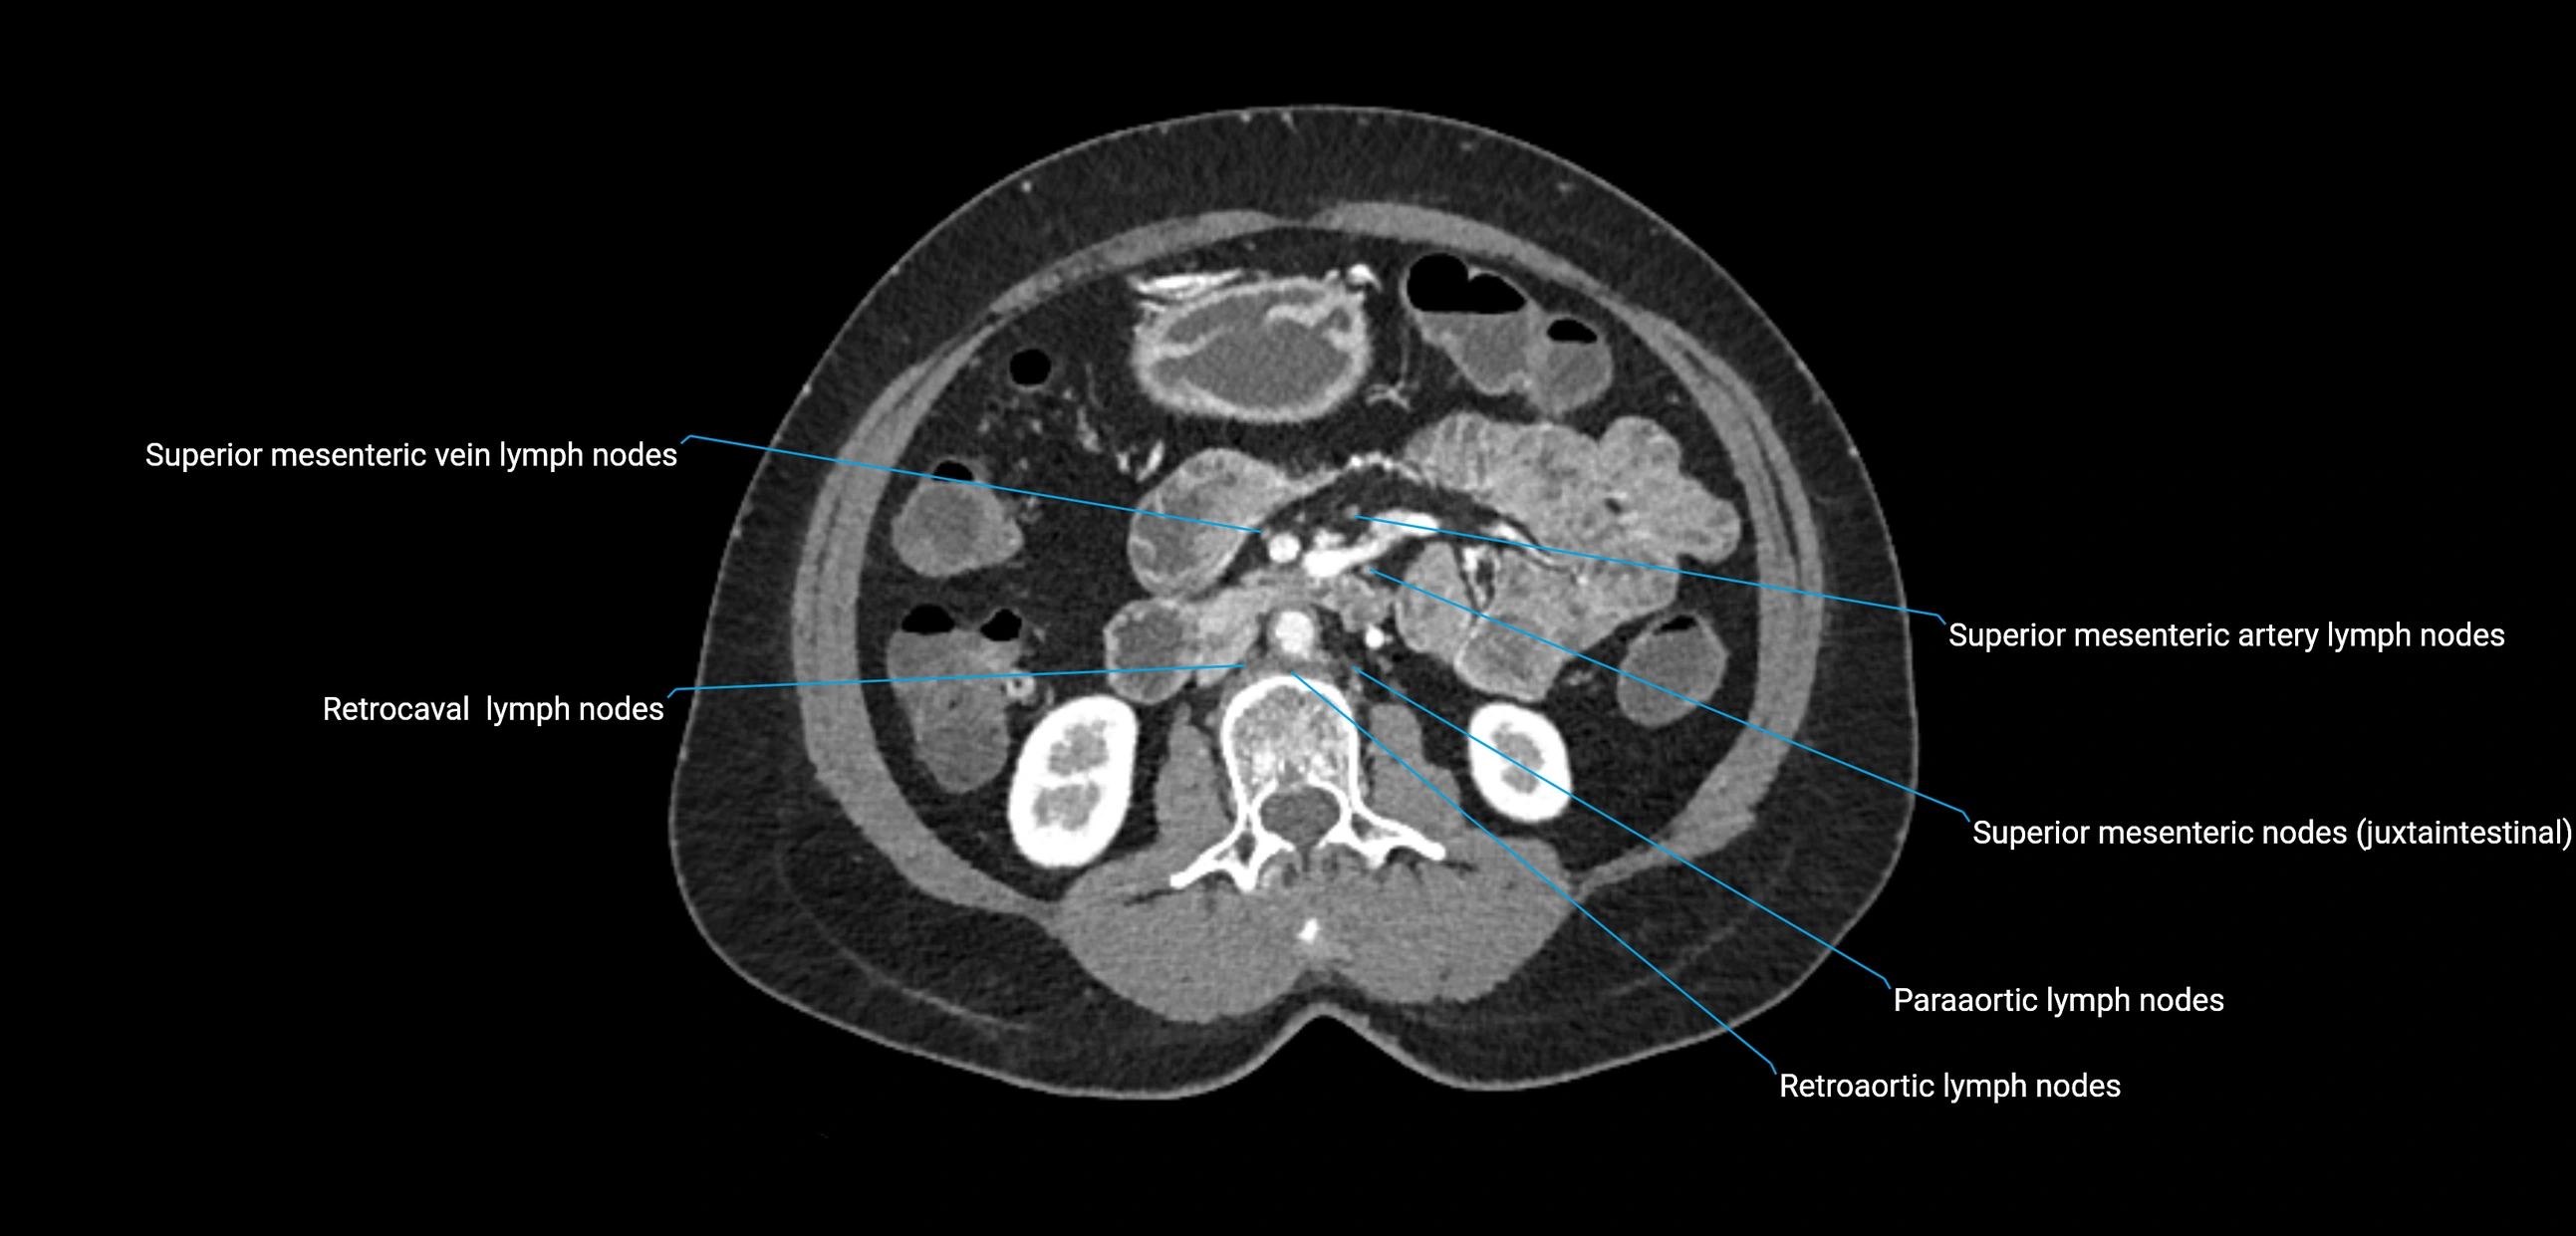

CT Appearance

CT Pre-Contrast:

• Nodes appear as soft-tissue density nodules adjacent to the aorta and IVC

• Calcification may be seen in chronic infections (e.g., tuberculosis)

CT Post-Contrast:

• Normal nodes enhance homogeneously

• Malignant nodes may show heterogeneous enhancement, central necrosis, or conglomerate formation

• Size >1 cm short axis is suspicious, though morphology and distribution are equally important